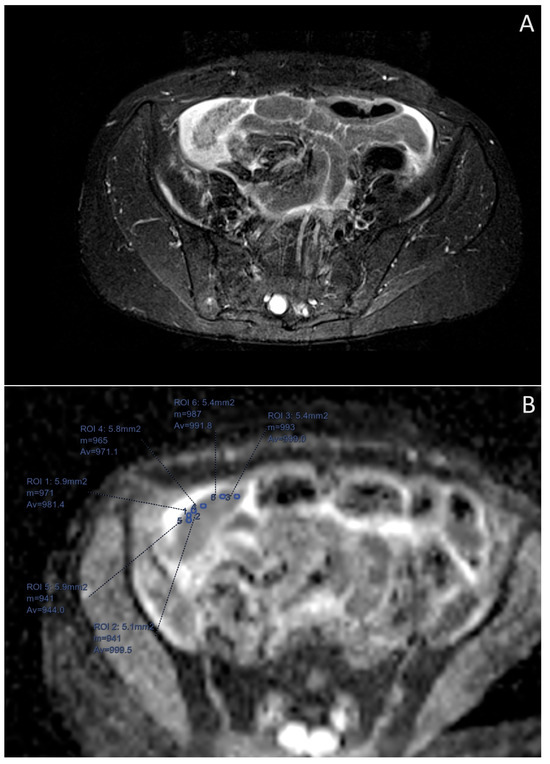

- Derlatka, P.; Grabowska-Derlatka, L.; Halaburda-Rola, M.; Szeszkowski, W.; Czajkowski, K. The Value of Magnetic Resonance Diffusion-Weighted Imaging and Dynamic Contrast Enhancement in the Diagnosis and Prognosis of Treatment Response in Patients with Epithelial Serous Ovarian Cancer. Cancers 2022, 14, 2464. [Google Scholar] [CrossRef]